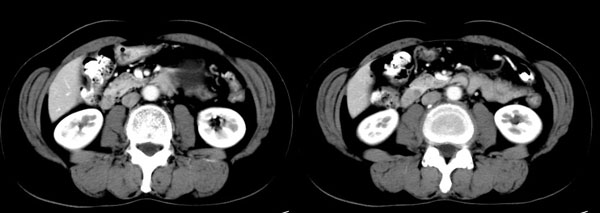

女性,58岁。卵巢癌术后4年余,无不适。体检b超发现左上腹肿块。

ct平扫加增强扫描:胆囊折叠,壁厚,其内见结石。胰腺体尾部见一5.8x7.5cm囊性肿物,ct值12hu,壁薄,增强扫描未明显强化,胰头不大,强化均匀。

ct诊断:1.胆囊炎,胆囊折叠并结石。

2.胰体尾部囊肿。